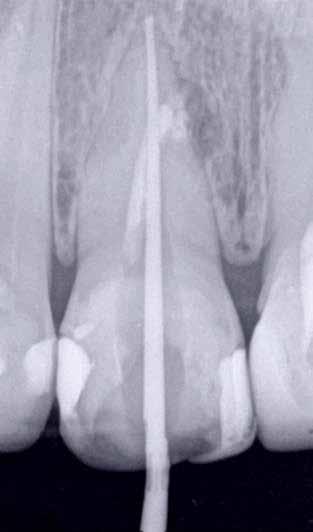

Hölgy páciensem az első konzultáció során tipikus kórtörténetet vázolt fel: Gyermekkora óta szeretett volna fogszabályozó készüléket, hiszen mindig is zavarta a class 2-es eltérésnél tipikusan jellemző nagy overjet (1-3. képek), és természetesen az ezáltal kifelé álló felső metszőfogai, részben a felső metszők protrúziója, részben pedig a disztálisan elhelyezkedő mandibula miatt. Annak ellenére, hogy több fogszabályozó szakorvosnál is járt az évek során, de mivel saggitális eltérése és az alsó metszőfogak torlódása miatt négy kisőrlőfog extrakcióját, illetve emellett sokszor állcsont műtétet is javasoltak neki, nem vágott bele a kezelésbe (4-5. képek).

A fogorvosa – nagyon helyesen – felhívta a figyelmét, hogy parodontális státusza is valószínűsíthetően romlani fog az eltérése miatt, újabb kört futott, immár 39 évesen, de még mindig premoláris fogak húzása és állcsontműtét nélkül szerette volna a fogszabályozást.

A konzultáció során arról is beszéltünk – ahogy az ilyenkor lenni szokott –, sohasem szeretett igazán mosolyogni, de a Pitts Protokolloknak köszönhetően az arc- és mosolyesztétikai céloknak megfelelően kerül megvalósításra az okklúziós korrekció. Az okklúziós kezelési célok az alábbiak voltak: a felső és alsó fogív nivellálása és tágítása, az alsó fogsor/ mandibula mezializálása, valamint a harapás megemelése által a mélyharapás rendezése.

A kezelést Pitts-21-es fogszabályozó készülék alkalmazásával végeztük el. A felső fogíven mosolyvonal beállító esztétikai (Smile Arc Protection - SAP), az alsó fogíven a Spee görbe kiegyenlítését szolgáló funkcionális bracket pozicionálást

alkalmaztunk. Előbbi elengedhetetlen a szép, íves mosolyvonal kialakításához, utóbbi pedig az alsó fogsor mezializálásához, és így az első osztályú sagittális okklúzió kialakításához. Az alsó metszők torlódásának feloldására tolórugókat alkalmaztunk az első hónapban (8. kép)